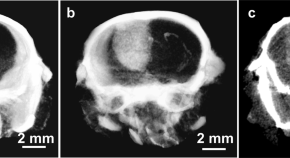

High concentrations of some types of plasma lipoproteins, such as low-density lipoprotein, promote atherosclerosis and a wide range of vascular-related diseases. These pathogenic lipoproteins have in common the protein component apolipoprotein B. Through study of the effects of modulating lipoprotein levels in experiments involving zebrafish, mice and cultured human endothelial cells, Inbal Avraham-Davidi et al. uncover a potentially deleterious role of apolipoprotein B–containing lipoproteins as direct inhibitors of the angiogenic behavior of vascular endothelial cells.